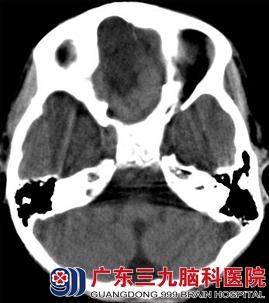

CT表现(图1、2):前颅窝底可见一等密度(与脑实质密度相同)占位性病变,其前方可见囊性的低密度影,与脑脊液密度相似,相邻脑组织受推压,未见明显水肿密度影。MR表现(图3-6):病变呈等T1等T2信号,边界清晰;其前方可见长T1长T2信号影,增强后,病变未见强化。弥散加权成像(DWI):未见病变弥散受限,前方囊性部分呈低信号。考虑为前颅窝脑外占位性病变。

图1 CT平扫:前颅窝底可见一囊性脑脊液低密度影